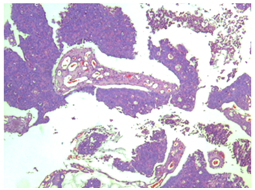

A 41-year-old male patient, who went to the Urology service of the Medical Center Lic. Adolfo Ruiz Cortines (IMSS) by macroscopic hematuria, no clots formation, associated with pain in the hypogastrium. He reported weight loss of 10 kg in three months. Physical examination was observed the abdomen with discrete volume increase in the hypogastrium and palpation a tumor of Approximately 5 cm, depending on the scar umbilical, mobile, not painful or fixed in the deep planes, slightly indurated. Laboratory studies reported cytometry hematics within the normal parameters; blood chemistry with glycemia of 164 mg/dL, urea of ​​40 mg/dL and creatinine 1.1 mg/dL. The general examination of urine with glycosuria, proteinuria, hemoglobin (+) and numerous erythrocytes. The ultrasound abdominal bladder showed a lobed image, of heterogeneous content adjacent to the upper wall. Abdominal-pelvic tomography (Figure 1) and (Figure 2) reported: free retroperitoneum lymphadenopathy, morphology of large vessels with normal diameter and path; in the cavity pelvic urinary bladder was observed with thickening from the wall and in the middle line the wall anterior with irregular, heterogeneous image, which was enhanced with the contrast medium, with towards the abdominal cavity and wall, 38 x 27 mm, with multiple calcifications Punctiform peripherals. (Figure 3) evidenced a tumor in the bladder dome of solid aspect, with zones of brown color, approximate diameter of 3 cm and irregular edges. The treatment consisted of Transurethral resection of the bladder, with results satisfactory.

Figure 1 Tomography (axial) showing multiple punctate peripheral calcifications.